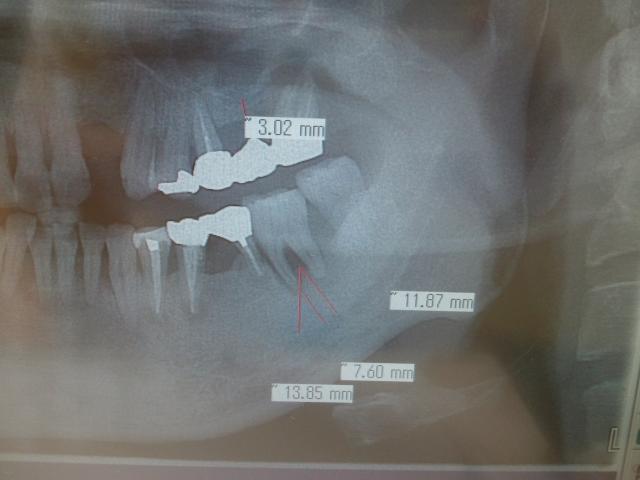

º¸²¼£·ÈÖ¡¡

È´»õ¨»þËäÆþ¡¡

¡¡¡¡¡¡¡¡¡¡¡¡¡¡Ä¾·Â£´¡¥£¸Ð¡ß£¸Ð¡¡£Ó£Ð¡¡

¥¹¥È¥í¡¼¥Þ¥ó¥¤¥ó¥×¥é¥ó¥È¿¢Î©

º¸¾å£¶ÈÖ¡¡

¥Õ¥é¥Ã¥×¥ì¥¹¥½¥±¥Ã¥È¥ê¥Õ¥ÈË¡

¼£ÎÅÊý¿Ë